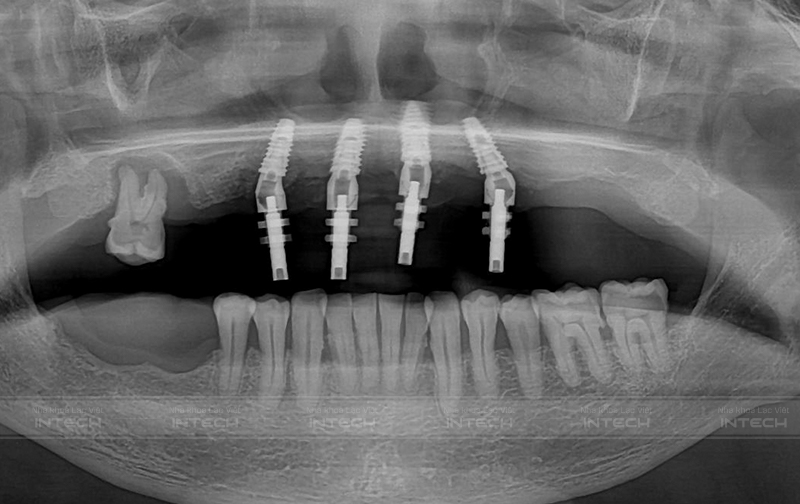

Các trụ implant sau khi cấy ghép

Sau khi cấy ghép trụ implant, khách hàng sẽ được khôi phục 12 hàm răng sứ với 12 răng, khôi phục khoảng 90 - 95% khả năng ăn nhai. Chú Trung cũng chia sẻ: "Các bác sĩ sợ chú đau nhưng thực sự là chú không thấy đau, về nhà chú cũng không cần dùng tới thuốc giảm đau. Chú đánh giá rất cao tay nghề của bác sĩ và công nghệ điều trị tại Nha khoa Lạc Việt Intech."